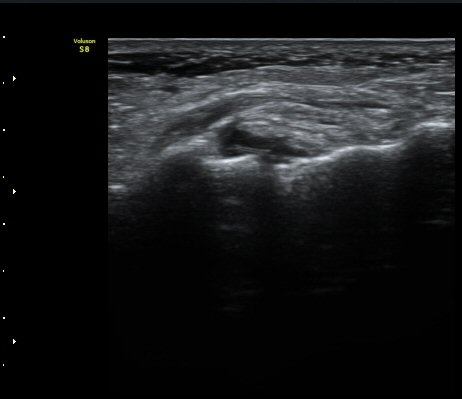

Á¾°ñÀÔ¹æ°ñÀÎ´ë ¿ÜÃø Á¾´Ü¸é°Ë»ç¿¡¼­ ¼ö¾×Àú·ù°¡ °üÂûµÊ(»çÁø 6, 7).